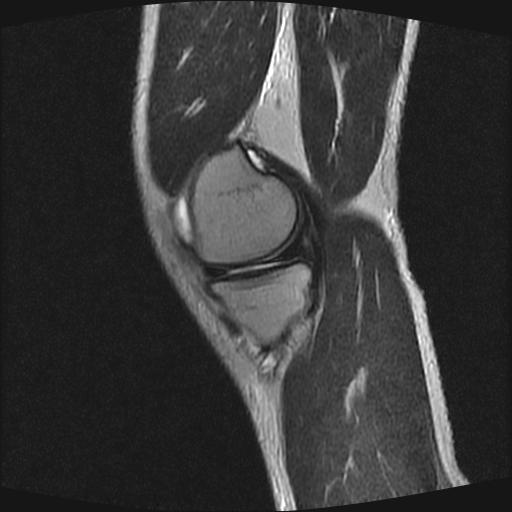

40岁男性,右膝关节外伤,x光平片示,髁间隆突撕脱骨折。

1、前交叉韧带撕裂;

2、外侧半月板后角撕裂;

3、关节腔积液。

前交叉韧带撕裂,关节腔积液.

半月板1-2级损伤   前交叉韧带撕裂伤   关节腔少量积液  诸骨未见新鲜外伤性改变

髁间隆突撕脱骨折;内侧副韧带损伤。

内侧副韧带撕裂及关节腔积液是肯定的,但是前交叉撕裂确定吗?会不会有容积效应的因素,因为前一张前交叉显示清楚,连续性良好,且较光滑。请问楼主有关节镜支持吗?我们医院也经常有这样的患者,但苦于没有关节镜,而无法对照、证实(除非完全断裂),出现了不同的诊断结果只能毫无意义的争论。

1、前交叉韧、内侧副韧带撕裂;

3、关节腔积液。4、髁间脊撕脱骨折。